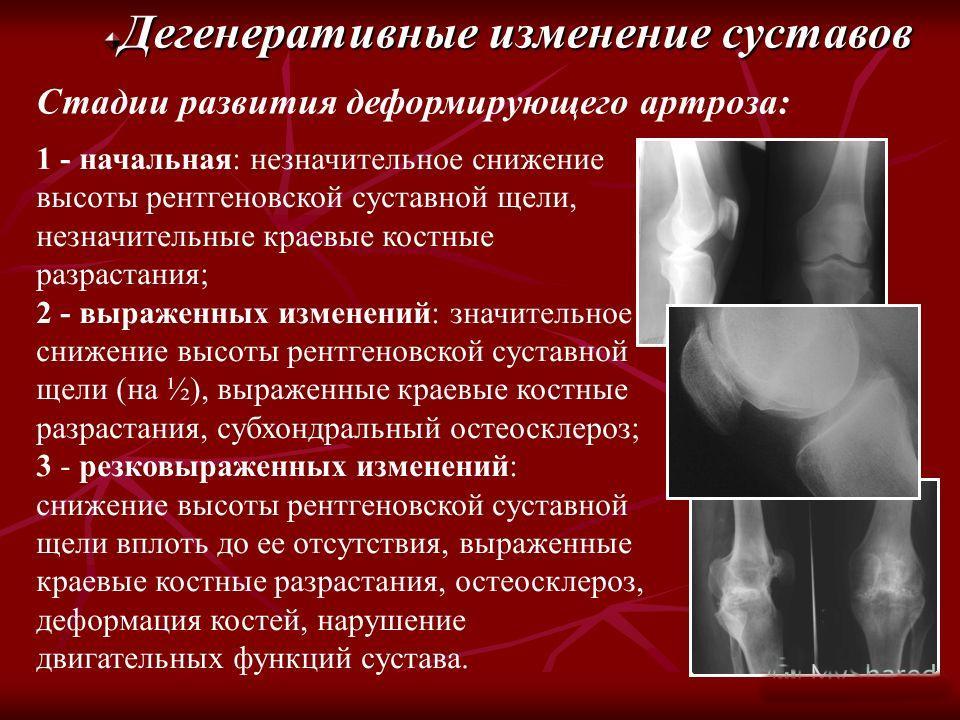

Остеоартроз является хроническим заболеванием суставов, в основе которого лежит дистрофическое изменение хрящевых тканей с их последующим разрушением и возникновением характерных деформаций. Хрящ истончается, становится шероховатым, растрескивается, теряет прочность и эластичность. В результате этого патологического процесса формируются краевые костные разрастания — остеофиты.

На рентгенограммах тазобедренный сустав сохраняет нормальную форму, суставная щель умеренно или неравномерно сужена с субхондральным склерозированием костных суставных поверхностей, непостоянными краевыми костными разрастаниями (I стадия).

Рентгенологически суставная щель может быть равномерно или неравномерно сужена, ацетабулярная суставная впадина уплощена, присутствуют явления субхондрального склероза, краевые костные разрастания. Конфигурация головки бедренной кости, как правило, не нарушена (II стадия).